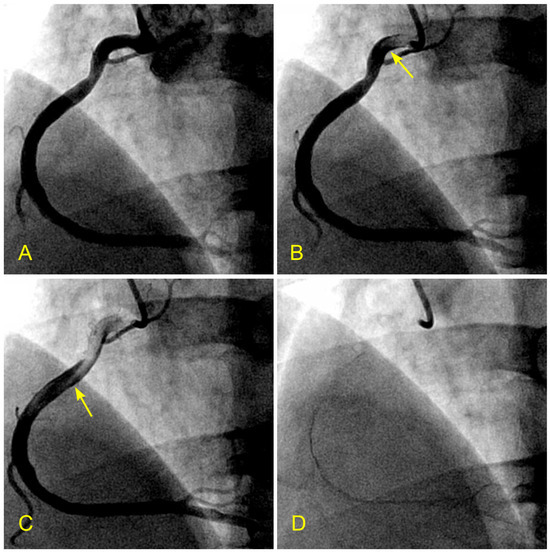

Figure 2.

(A–D) Arterial phase. These images are not in consecutive sequence. (A) The artery is full of contrast in black. (B) The blood, in white, begins to move in (arrow). (C) The blood, in white, moves to the mid-segment. The tip of the blood flow is pointed, which is typical for laminar flow (arrow). (D) The contrast in black is almost washed out of the artery. This is the end of the arterial phase.